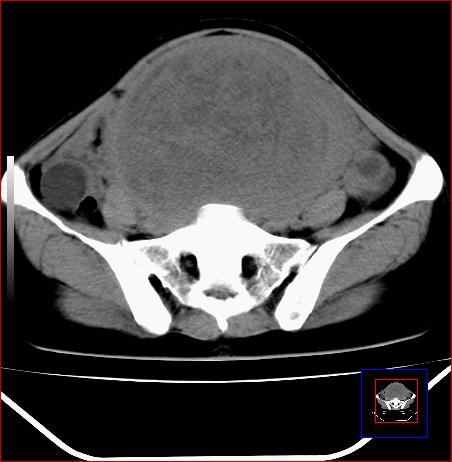

标题: CT15141:子宫肌瘤还是卵巢肿瘤 [打印本页]

标题: CT15141:子宫肌瘤还是卵巢肿瘤

腹部包块1年余,近两月明显增大,月经量多

与子宫关系密切,子宫肌瘤/子宫癌。

病灶呈实性包块,边界清晰,似与子宫分界不清,密度低于肌肉,考虑:恶性可能,确诊需要妇科诊刮。

子宫占位,恶性可能----肉瘤?

源于子宫的肿瘤,性质待定。恶性可能性大。